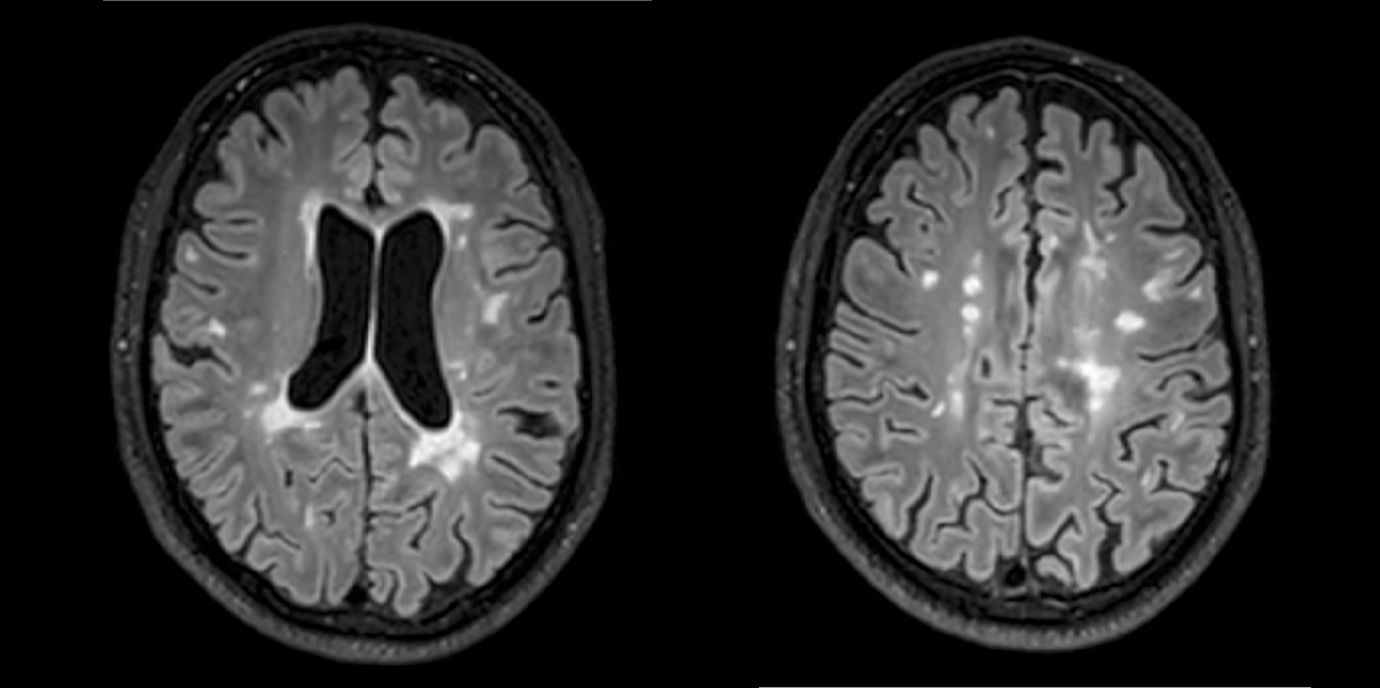

Die Ergebnisse einer neuen Multicenterstudie zu Multipler Sklerose könnten die Therapie dieser chronisch entzündlichen Erkrankung entscheidend verbessern. Forschende der Medizin Unis Innsbruck und Wien sowie des Inselspitals, Universitätsspital Bern belegen, dass zwei oder mehr in der Magnetresonanztomographie (MRT) sichtbare Läsionen im Gehirn innerhalb eines Jahres für eine Therapieintensivierung sprechen. Damit liegen erstmals eindeutige und evidenzbasierte Kriterien für eine Therapieanpassung vor.

Abseits klinischer Symptome, die von Einschränkungen des Sehvermögens bis hin zu Lähmungserscheinungen ein breites Spektrum umfassen, kann die Krankheitsaktivität bei MS auch bildgebend dargestellt werden. „Der Nachweis entzündlicher Läsionen im Gehirn mittels MRTerlaubt auch eine Einschätzung geringerer Krankheitsaktivität, denn vermeintlich stabile Patient:innen können trotz Therapie weiterhin neue, klinisch stumme, entzündliche Veränderungen entwickeln“, weiß Neuroimmunologe Harald Hegen, der an der Innsbrucker Univ.-Klinik für Neurologie bereits seit vielen Jahren zu MS forscht.

In die Studienkohorte wurden 131 MS-Patient:innen aus MS-Zentren in Österreich und der Schweiz eingeschlossen, die unter einer gering- bis moderat-effektiven Immuntherapie zwölf Monate lang klinisch stabil waren und dann einer MRT unterzogen wurden. „Wir konnten zeigen, dass Patient:innen mit schubförmiger MS, die unter Immuntherapie zwei oder mehr neue entzündliche MRT-Läsionen innerhalb eines Jahres entwickeln, auch bei klinischer Stabilität, also ohne Symptome, von einem Wechsel auf eine hoch-effektive Immuntherapie profitieren“, beschreibt Erstautor Gabriel Bsteh von der Medizinischen Universität Wien die zentrale Erkenntnis. Damit liefert die Studie eine für den klinischen Alltag wichtige Erkenntnis, die für die individuelle Therapieanpassung genutzt werden sollte.

„Nachdem Läsionen oft schon vor dem Auftreten klinischer Symptome in der MRT sichtbar sind, ermöglicht eine bildgebende Kontrolle bei Patient:innen mit einer gering- bis moderat-effektiven Therapie ein frühes Eingreifen in den individuellen Krankheitsverlauf“, betont Studienleiter Harald Hegen. In der Studienkohorte waren rund 40 Prozent der Patient:innen klinisch stabil, zeigten allerdings in der MRT schon eine oder mehrere Läsionen. Bislang war in der klinischen Praxis eine Therapieverstärkung nur nach Auftreten klinisch manifester Symptome angezeigt.